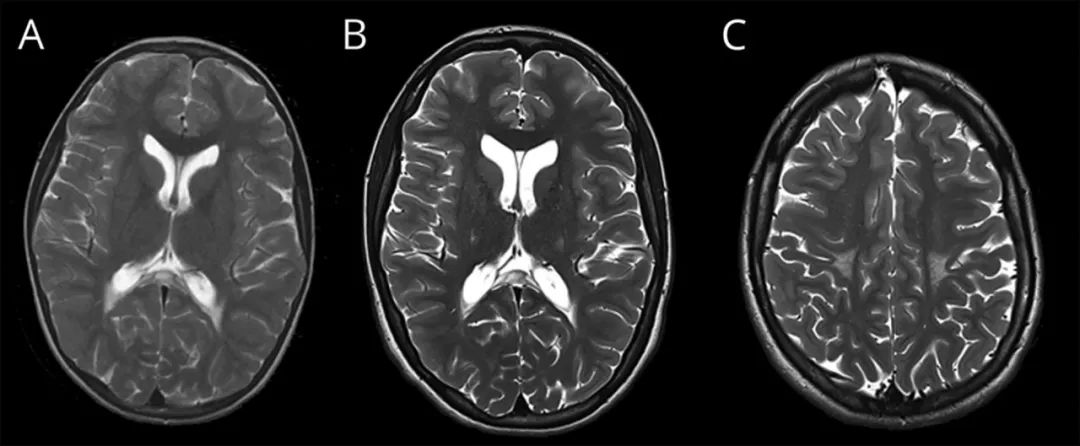

实验室检查显示血细胞计数、维生素水平(B12,叶酸,E)、乳酸、葡萄糖、肾、肝和甲状腺功能、C反应蛋白、高半胱氨酸、甲基丙二酸和铜均正常。排除了因B12和铜缺乏引起的脊髓病的可治疗原因;胆甾烷醇水平未检查。极长链脂肪酸正常,使得肾上腺脊髓性神经病变型的可能性较小。在第一次评估期间进行的脊柱MRI未见明显异常,为此未复查。头颅MRI显示胼胝体和侧脑室周围非增强、融合性对称性白质病变,与之前的MRI相比没有太大进展(图1)。

图1 患者头颅MRI影像。T2显示脑室周围融合性白质高信号(A,B)和皮层投射纤维高信号病变(C;第一次扫描中没有这些变化)。A为2007年扫描结果;B和C为2018年扫描结果。